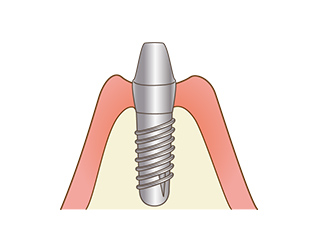

インプラントは、人工の歯根を埋め込み、人工の歯を装着することで失ってしまった歯を取り戻す治療方法です。

見た目の改善だけではなく、ご自身の歯と同じようにしっかりと噛むことができるため、機能面の回復も期待できます。

骨の中に穴をあけ、インプラント体を埋入する手術をします。埋入後はインプラントと骨が結合するのを待ちます。

インプラントと顎骨がしっかりと結合できたことが確認できたら、再度歯肉を開き、インプラントにアバットメント(土台)を取り付けます。